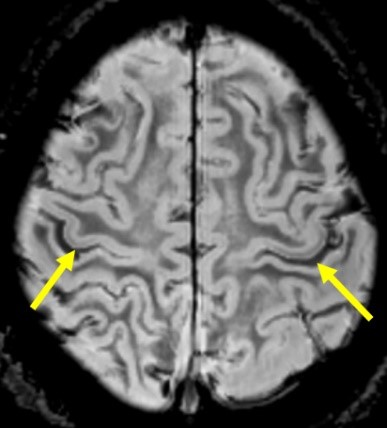

広範囲な脳形成異常の範囲の術前マッピング(カンファレンスに使用)

神経核内封入体病(NIID) 海馬硬化症

大脳の皮髄境界の高信号域 海馬の萎縮と高信号 T2強調像